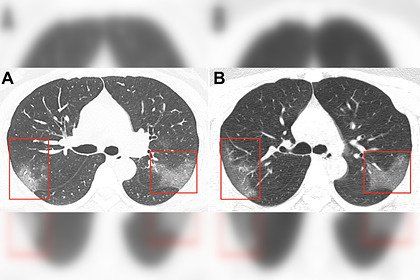

عرض الأطباء الصينيون، صورا لرئتين مصابتين بفيروس كورونا 2019-nCoV. وتم نشر نتائج التصوير الطبقي المحوري لمريضة تبلغ من العمر 33 عاما في مجلة Radiology

وعلى أساس الخصائص الوبائية، والأعراض السريرية ونتائج التصوير الطبقي المحوري، تم تشخيص إصابتها بالالتهاب الرئوي 2019-nCoV.

وبعد ثلاثة أيام من العلاج، زادت المنطقة المصابة من الرئتين (الصورة ب) – في الصور تبدو معتمة.